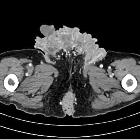

treatment of paraneoplastic hypercalcemia in a patient with giant condyloma acuminatum: a case report. Extract of pelvis computed tomography scan showing a destructive, polycyclic growing tumor. This is a picture of a computed tomography scan that we made to exclude bone metastasis. It shows the tumor mass, growing from the anal region (below in the picture) to the groin region (above). Furthermore it shows the local destructive grow-pattern.

An

extraordinary case of Buschke–Lowenstein tumor: multiple localization, malignant transformation, and clinical insights—a case presentation and literature review. CT image of the inguinal lesion. CT image was done for further investigation of hypercalcemia